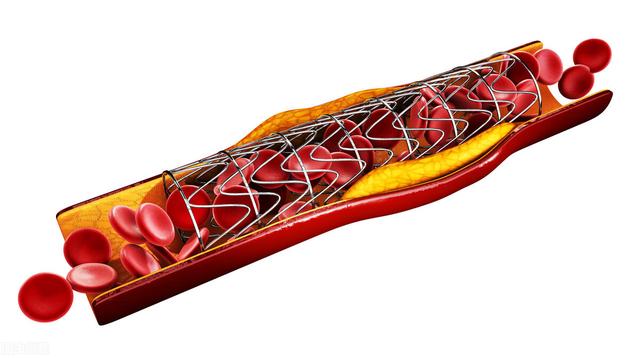

私たちは皆、多かれ少なかれ知っているはずだ。冠状動脈性心臓病とは、主に心臓の冠状動脈が狭くなる病気である。心臓に血液を供給する血管の狭窄は、心筋虚血や心筋壊死を引き起こす可能性があり、この狭窄を解消して冠動脈への血液供給を回復させるために、治療法のひとつは次のようなものである。何か支えとなるものを持っていく。それこそが、今、私たちが話しているブラケットなのだ。

ステップ3:軌道を確立する。最初のガイドワイヤーは冠動脈より太いので、この時は細いガイドワイヤーを選んで冠動脈病変の遠位部を通過させ、まずバルーンで拡張しなければならない。

ステップ4:ステントを留置する。バルーンの拡張が完了したら、このガイドワイヤーに従ってステントを留置する。

ひとつは心臓ステント自体の問題だ。また、ステントを留置した場所に再狭窄が生じることもあり、発生率は高くはありませんが、このステントを留置して数年後には、内外再狭窄のリスクがあります。